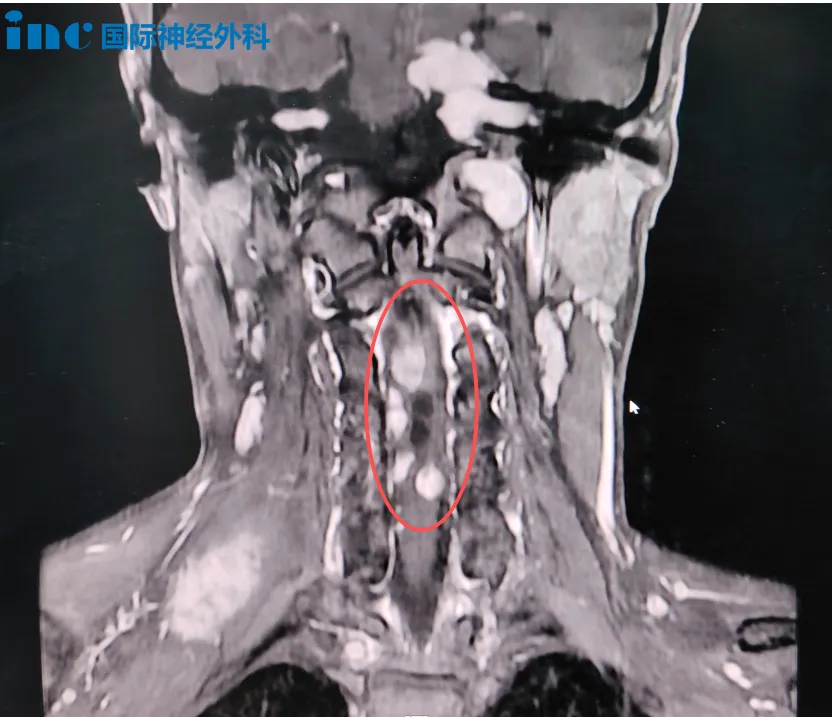

今日,在苏州大学附属第四医院,帆帆顺利进行高位颈髓占位病变手术。

颈髓是大脑、小脑与脊髓、周围神经相互联系的重要通路,其功能非常重要,一旦损伤将导致患者高位截瘫,甚至导致患者终身与呼吸机相伴等严重并发症。所以颈髓手术风险极大、对显微操作技巧要求极高。

帆帆的情况更是复杂,从颈髓内,到颈髓外,均有病变。

面对如此境况,抉择无比艰难。“要不要手术?风险有多大?”家人的忧虑,既关乎孩子的当下,更牵系着他漫长的未来。但在与巴教授深入沟通后,他们了解到,颈髓的病灶已是不得不闯的“关隘”。原来,帆帆罹患神经纤维瘤病2型,后颅窝、颈髓、腰骶部多个占位性病变,听神经瘤、脑膜瘤、室管膜瘤、囊肿等多个类型,需要分多次手术应对多处病灶。由于颈髓病灶持续进展可能面临瘫痪风险,首次手术将优先处理该部位。一家人迎难而上,坚定选择手术。

术中,巴教授首先精准地切除了帆帆髓外多个由系带连接的鞘瘤,清除了第一重危机。而真正的挑战,在于髓内——与正常神经组织纠缠不清的肿瘤,边界模糊。凭借精湛的显微技术与根植于心的神经保护理念,巴教授在方寸之间耐心探寻,最终在肿瘤与正常组织之间找到分界,实现了令人满意的切除。